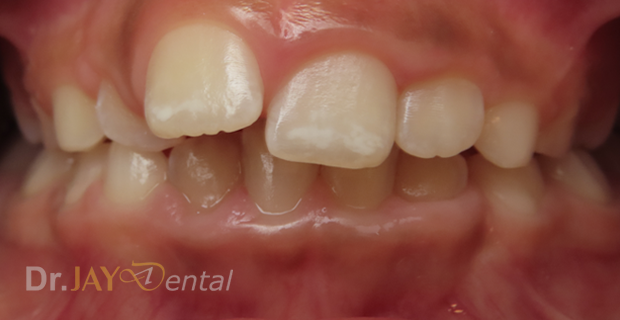

CASE 16

Misaligned teeth , crowding resolving in 3 months , patient still continuing with treatment. Arch expansion and myofunctional therapy

Before

After